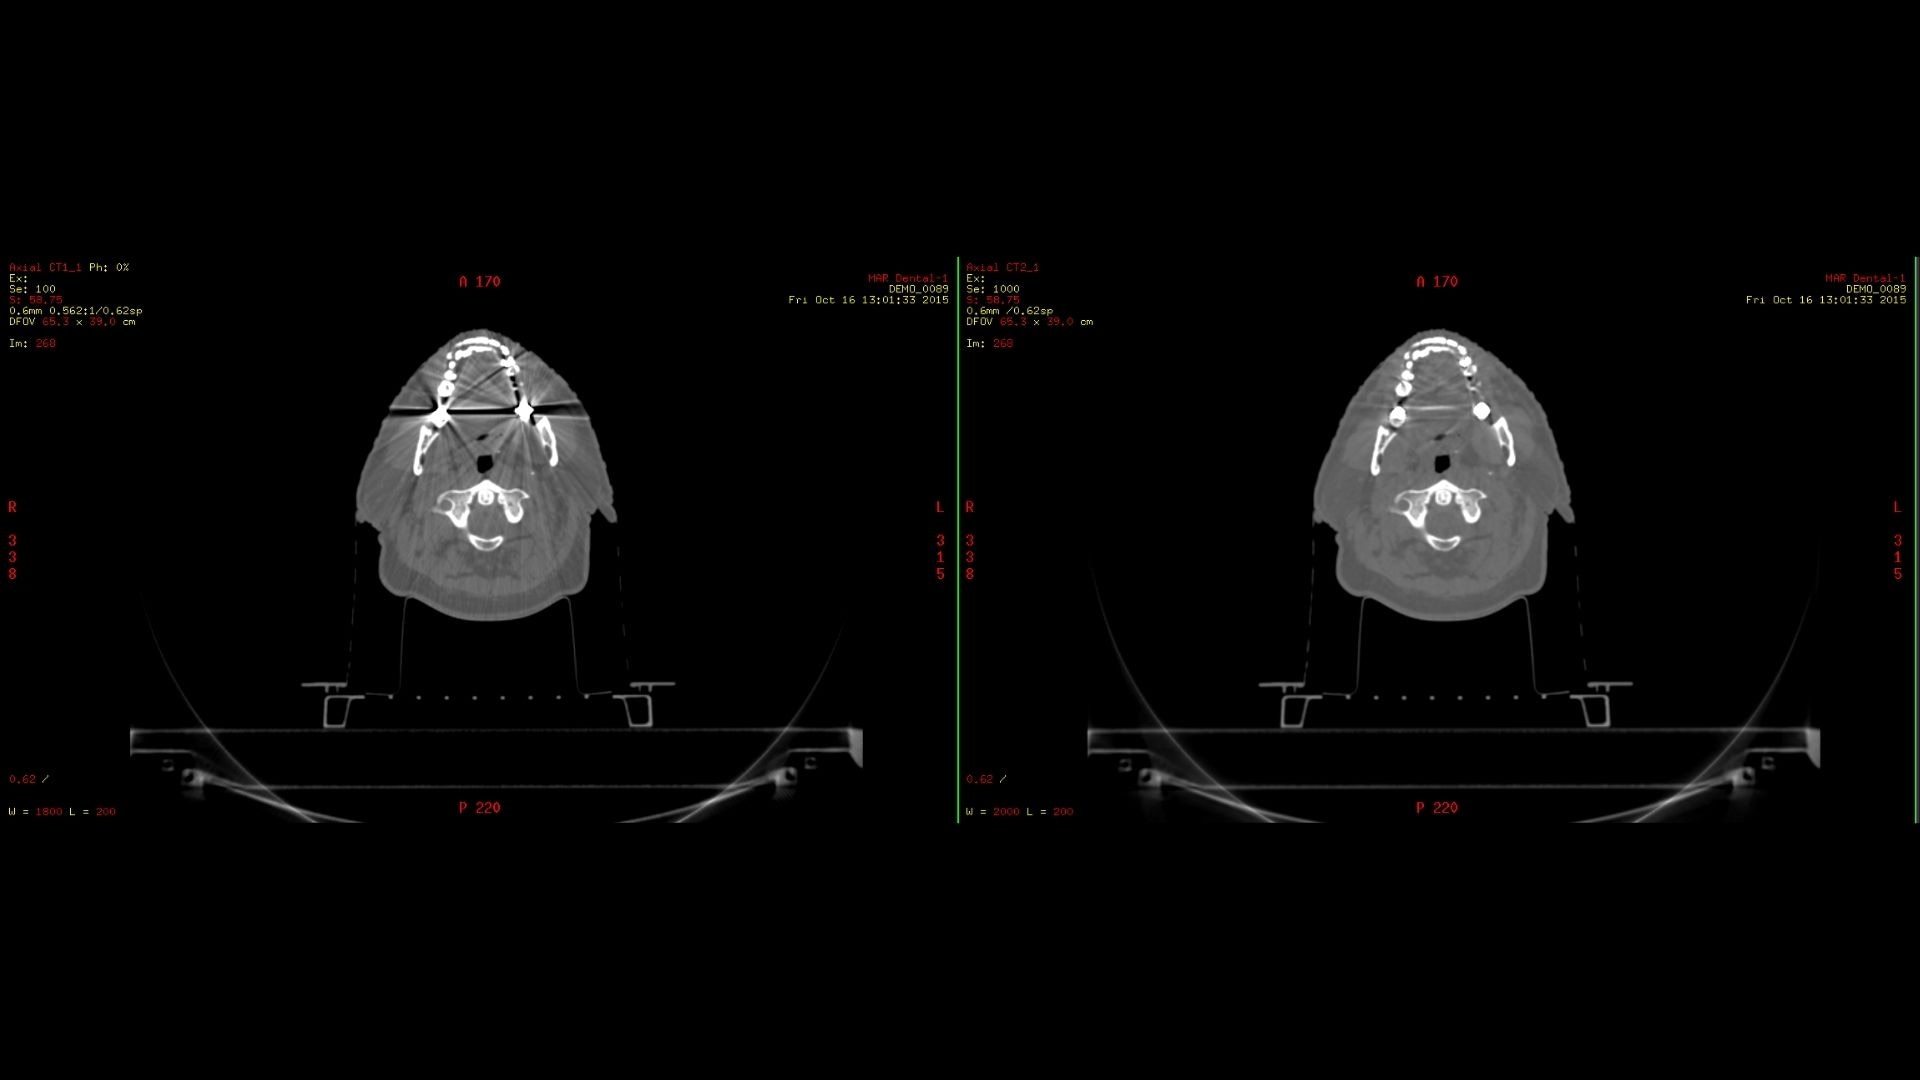

Smart MAR 2.0

Smart MAR 2.0 is designed to reduce artifacts of high-density materials, including orthopedic implants, dental fillings, and other metal in the body. Our metal artifact correction technology is based on raw data, enabling you to reduce artifacts caused by both photon starvation and beam hardening, revealing the anatomy that was concealed all the way out to the edge of the bore.